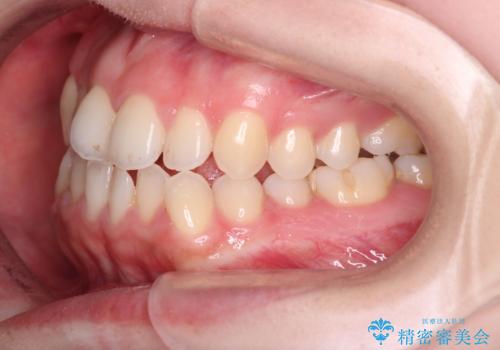

- 前歯の凸凹を主訴に来院された患者様です

骨格性の下顎前突傾向もあったため、臼歯関係の遠心移動も行うことで綺麗な仕上がりで矯正を終了することができました。

遠心移動を行うことで期間はかかりましたが、良い状態で仕上がっています。